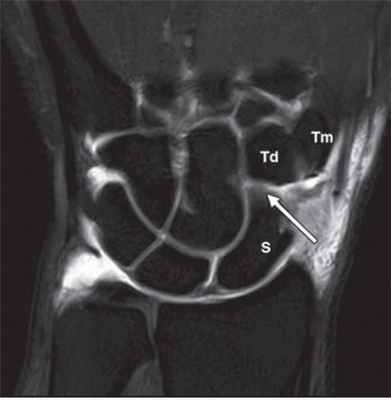

МРТ кисти. Корональная Т1-взвешенная томограмма с подавлением сигнала от жира. Ладьевидно-трапецевидная связка в норме. Обозначения: S- ладьевидная кость, Td – трапециевидная кость, Tm – трапеция.